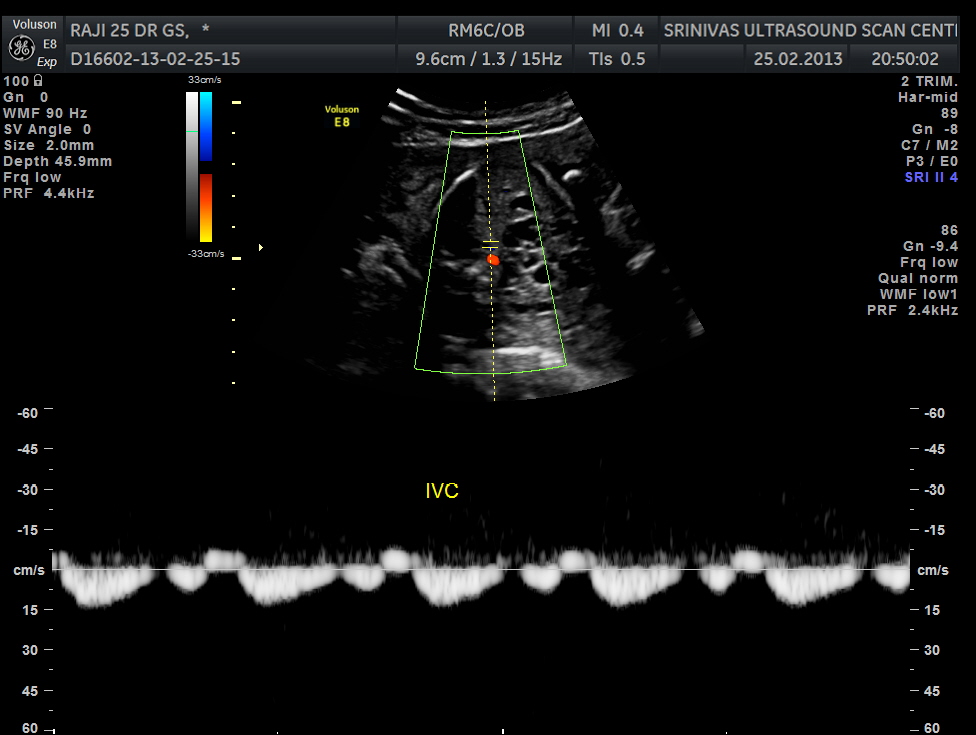

Abdominal transverse view shows aorta and ivc in juxtaposition and on the right side . This is suggestive of heterotaxy – right atrial isomerism. Grossly enlarged dysplastic left kidney is also seen. Right fetal kidney is difficult to visualise in this view. Stomach is in the midline. Heart is on the right side of the chest- dextrocardia

spectral doppler showing aortic flow (above ) and ivc flow ( below image ).